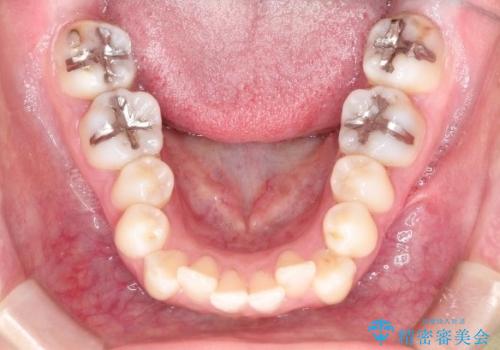

初診時の歯並びの状態としては、上下ともに前歯部の中等度のがたつきがあり、特に左上の前歯が1本内側に入り込んでしまっている状態でした。

抜歯なし/インビザラインによるマウスピース矯正にて治療を行いました。

内側に入り込んでしまっている歯を出してくることに非常に時間がかかりましたが、一度歯を歯茎の方へ押し込みそして前へ出してくる2段階の治療を行いました。